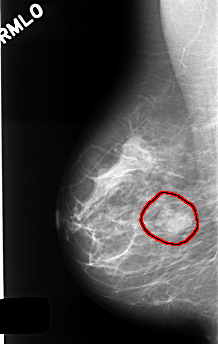

C_0415_1.RIGHT_CC

FILE: C_0415_1.RIGHT_CC.OVERLAY

TOTAL_ABNORMALITIES 1

ABNORMALITY 1

LESION_TYPE MASS SHAPE LOBULATED MARGINS CIRCUMSCRIBED

ASSESSMENT 4

SUBTLETY 5

PATHOLOGY BENIGN

TOTAL_OUTLINES 1

BOUNDARY